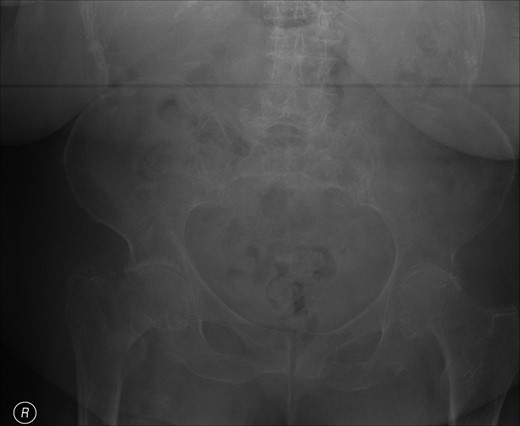

Post-operative nausea delayed immediate attempts at rehabilitation. Although she sat out in a chair, transfers were accomplished with a hoist. At 10 days, post-operatively she was transferred to a peripheral hospital, where rehabilitation commenced with a 2-min period of standing with support. The following morning she complained of greatly increased pain in the operated hip. A radiograph showed that the screw had separated from the barrel, as shown in Fig. 3.

The patient was referred for surgical revision and was treated with a total hip arthroplasty. She made a satisfactory recovery.